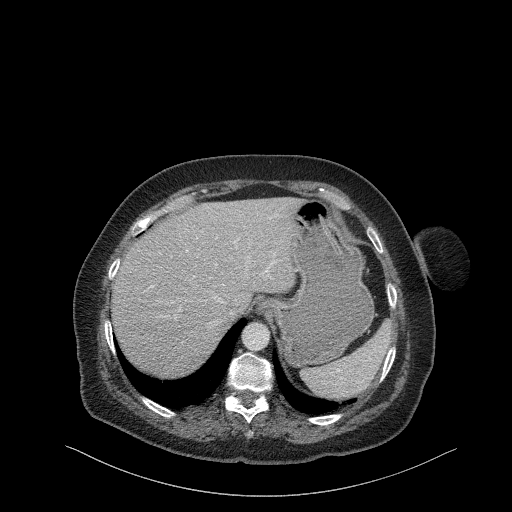

Original NATIVE CT scan (input)

No window - Raw intensity values

Lung window (WL -600, WW 1500 β†’ Low βˆ’1350, High +150)

Mediastinum window (WL 40, WW 400 β†’ Low βˆ’160, High +240)